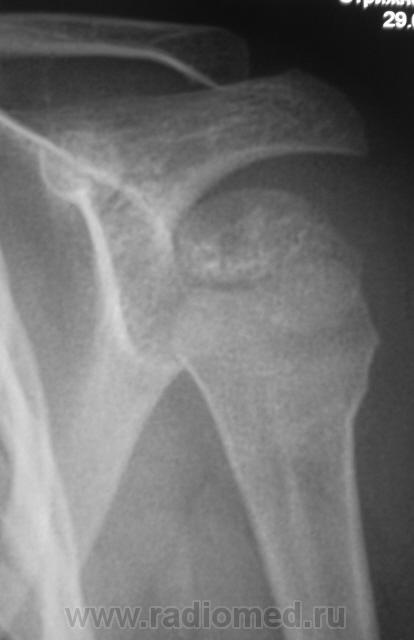

Да, дети разные.

Это у меня нижняя группа снимков не загрузилась - решил верхние - двух человек...

Но у первого пострадавшего помимо перелома и вывиха в плечевом ещё и надрыв/разрыв ключично-акромиального сочленения.

На мой взгляд, вывих спорный.

В обоих случаях перелом хирургической шейки плечевой кости. А почему только в одной проекции? Мы всегда снимаем в двух - в прямой и аксиальной.